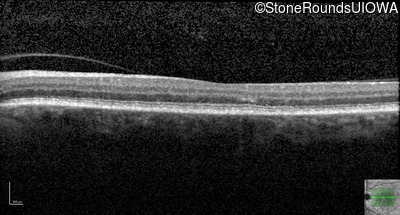

Age at visit: 59 years (Visit 3)